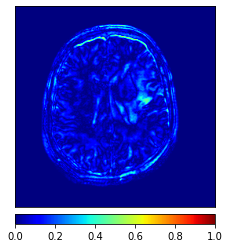

In this paper, we propose a bidirectional learning model, known as dual contrast cycleGAN (DC-cycleGAN), for medical image synthesis from unpaired data. Specifically, a dual contrast (DC) loss is formulated that leverages the advantage of samples from the source domain as negative samples to indirectly build constraints between real source and synthetic images via discriminators, and synthesize images more related to the target domain by enforcing the synthetic images to fall far away from the source domain. In addition, structural similarity index (SSIM) [35] and cross-entropy (CE) [48] are integrated into the DC-cycleGAN structure to avoid disappearing gradient information that is caused by a mean absolute error (MAE) and synthesizing irrelevant images. SSIM considers luminance [35] and CE converges fast as its back-propagation error is less than MSE [28]. As can be seen in Figs. 1 and 2, using SSIM and CE with dual contrast can generate more clear and accurate MR images as compared with that of MAE and MSE, and SSIM and CE without dual contrast loss. Although both SSIM and CE with dual contrast and without dual contrast generate similar CT images, SSIM and CE with dual contrast quantitatively generate better images as shown in Table 4. The experimental results indicate that DC-cycleGAN is able to consider more complex features such as structure in synthesizing images and produce remarkable results as compared with other state-of-the-art methods reported in the literature.

Moreover, Figs. 6 and 7 show the synthesized MR and CT images along with the errors between the real and synthesized images by different methods, respectively. It can be seen that the synthesized images by DC-cycleGAN are more identical to the real ones as compared with other methods. This indicates that effectiveness of SSIM and CE along with dual contrast in synthesizing images. In addition, the error between the groundtruth and synthesized MR/CT images by DC-cycleGAN is relatively less as compared with other methods.

Tables 3 and 4 show the results of MR and CT synthesis, respectively. As can be seen, all components play vital role in both tables. SSIM & CE (w) performs significantly better than other losses in synthesizing MR images. This also can be seen visually in Fig. 1. In contrast, SSIM&CE (w) performs slightly better than SSIM&CE (wo) in synthesizing CT images, both generate more or less similar CT images (see Table 4).